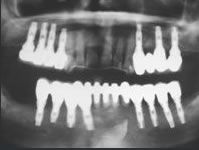

Nous maîtrisons tous les types d’implants :

Biomet 3i Encode, Biomet 3i Cam StructSURE, Simeda, Atlantis / Astra Tech, Anthogyr, Keystone, Ankylos, Nobel, Straumann, etc.

Les systèmes Biomet 3i Encode et Cam StructSURE ainsi que Simeda permettent un ajustement et une réalisation sur mesure de votre pillier implantaire.

En fonction des cas et des indications, divers matériaux sont disponibles pour les pilliers implantaires : titane, zircone blanche, zircone teintée, etc…